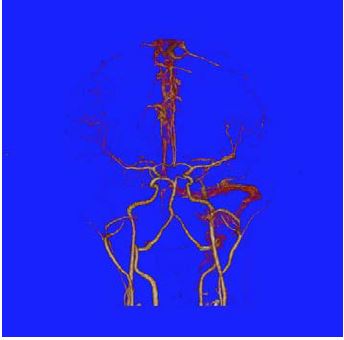

Al ingreso manifestaba intenso dolor cervical, afasia motora, desviación de la mirada a la derecha, sialorrea, hemiparesia izquierda, Babinsky izquierdo, reflejo rotuliano izquierdo exaltado y no mostraba alteración en la sensibilidad ni signos meníngeos. Su talla es de 173 cm (por encima del percentil 95), delgada, extremidades largas y con aracnodactilia. El TAC cerebral simple evidenció trombosis de varios senos venosos (figura 1); el estudio se complementó con Angio TAC cerebral (figura 2), resonancia magnética cerebral (figura 3) y Angio resonancia cerebral contrastada (figura 4), que confirman la trombosis de los senos venosos. Después de diagnosticar accidente isquémico se trasladó a la unidad de cuidados intensivo (UCI) y se anticoagula con enoxaparina. No necesitó soporte inotrópico ni ventilatorio y posteriormente se llevó a pisos. El ecocardiograma y el doppler carotideo fueron normales. No se encontró dislipidemia y el estudio de enfermedad autoinmune fue negativo. Los exámenes para trombofilia, tomados en etapa aguda, solo mostraron una proteína S ligeramente disminuida (57 %, VN de 59 a 118 %), al igual que la antitrombina m (58,8 %, VN 83-128 %). Se ampliaron estudios con ácido fólico y vitamina B12 en sangre, al igual que los ácidos orgánicos en orina por cromatografía; todos estaban normales. Los aminoácidos en sangre mostraron elevación de la metionina (63 µmol/L, VN de 10 a 45 µmol/L) y la homocisteina (3 µmol/L, VN de 0 a 1 µmol/L) con cistationina baja (0, VN de 0 a 3 µmol/L). El estudio de homocisteina en sangre fue de 214 µmol/L (VN en mujer de 5,08 A 15,39 µmol/L), lo que confirmó el diagnóstico de homocistinuria por deficiencia de CBS.